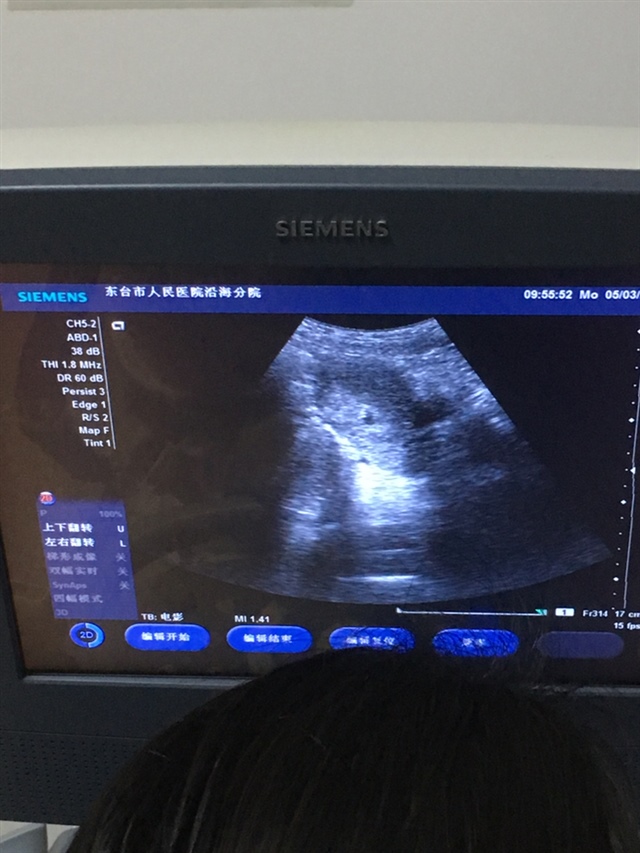

孕20周+5天

等一个星期后去复查